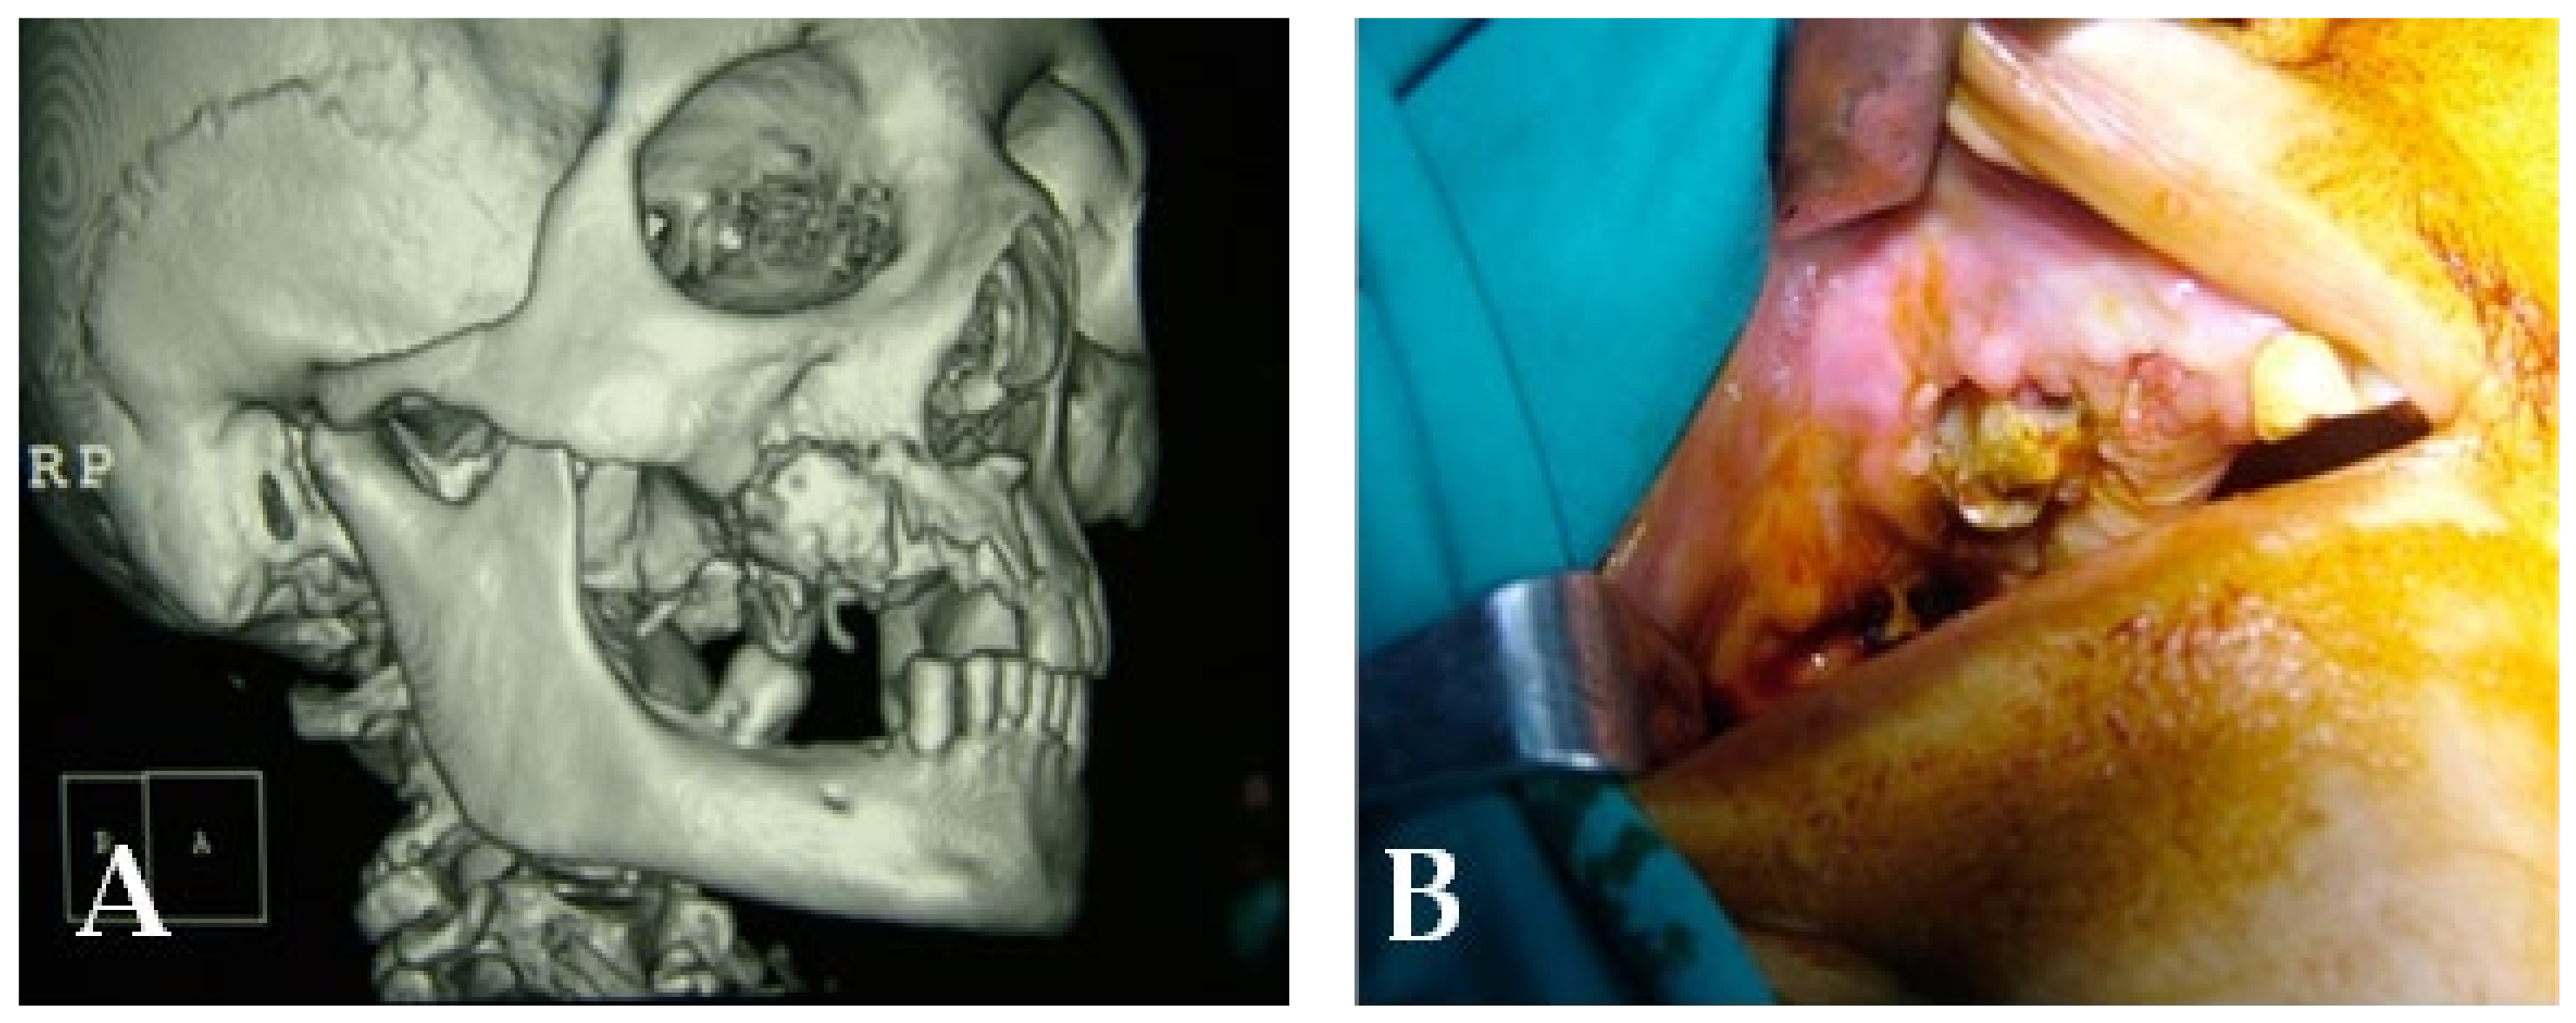

3.4. Clinical Case 4

3.5. Clinical Case 5